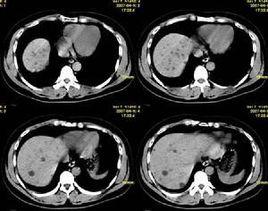

先天性兒童腎病患者的腎臟體積及重量是正常腎臟的2-3倍,腎單位也明顯增多,光鏡下沒有特異性的病變,生後1月腎臟可出現皮質小管囊性改變和增生性腎臟損害,最終小囊中的上皮細胞扁平,刷狀緣結構消失,小管萎縮,晚期可見中末期腎病病理改變。免疫螢光學檢查一般陰性,但在腎小球硬化區可見IgM和C3沉積,電鏡所見幾乎與年長兒腎病綜合徵無異,即腎小球上皮細胞足突融合。